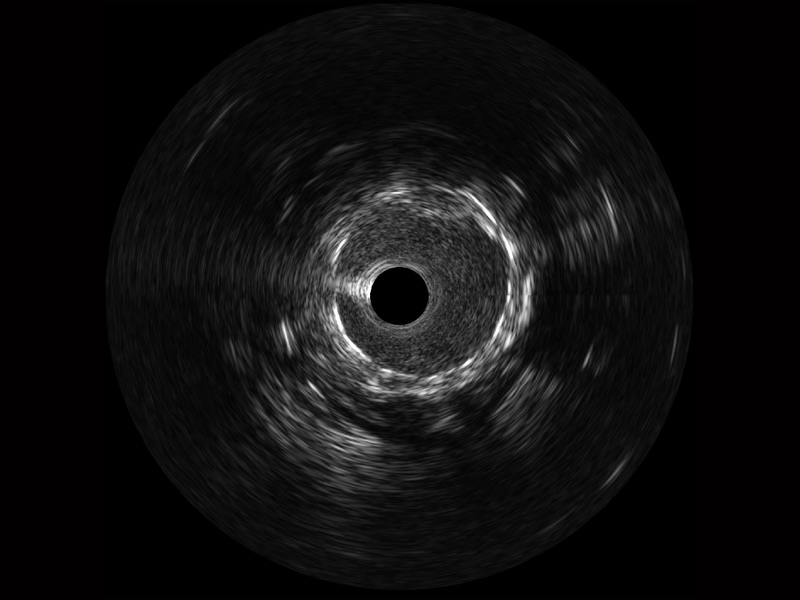

開立寬頻IVUS圖像

對比傳統(tǒng)IVUS導(dǎo)管成像,開立寬頻IVUS圖像的近場支架梁顯影更細(xì)膩,遠(yuǎn)場中膜外血管仍清晰可辨,兼顧遠(yuǎn)中近,兼顧分辨力與穿透深度